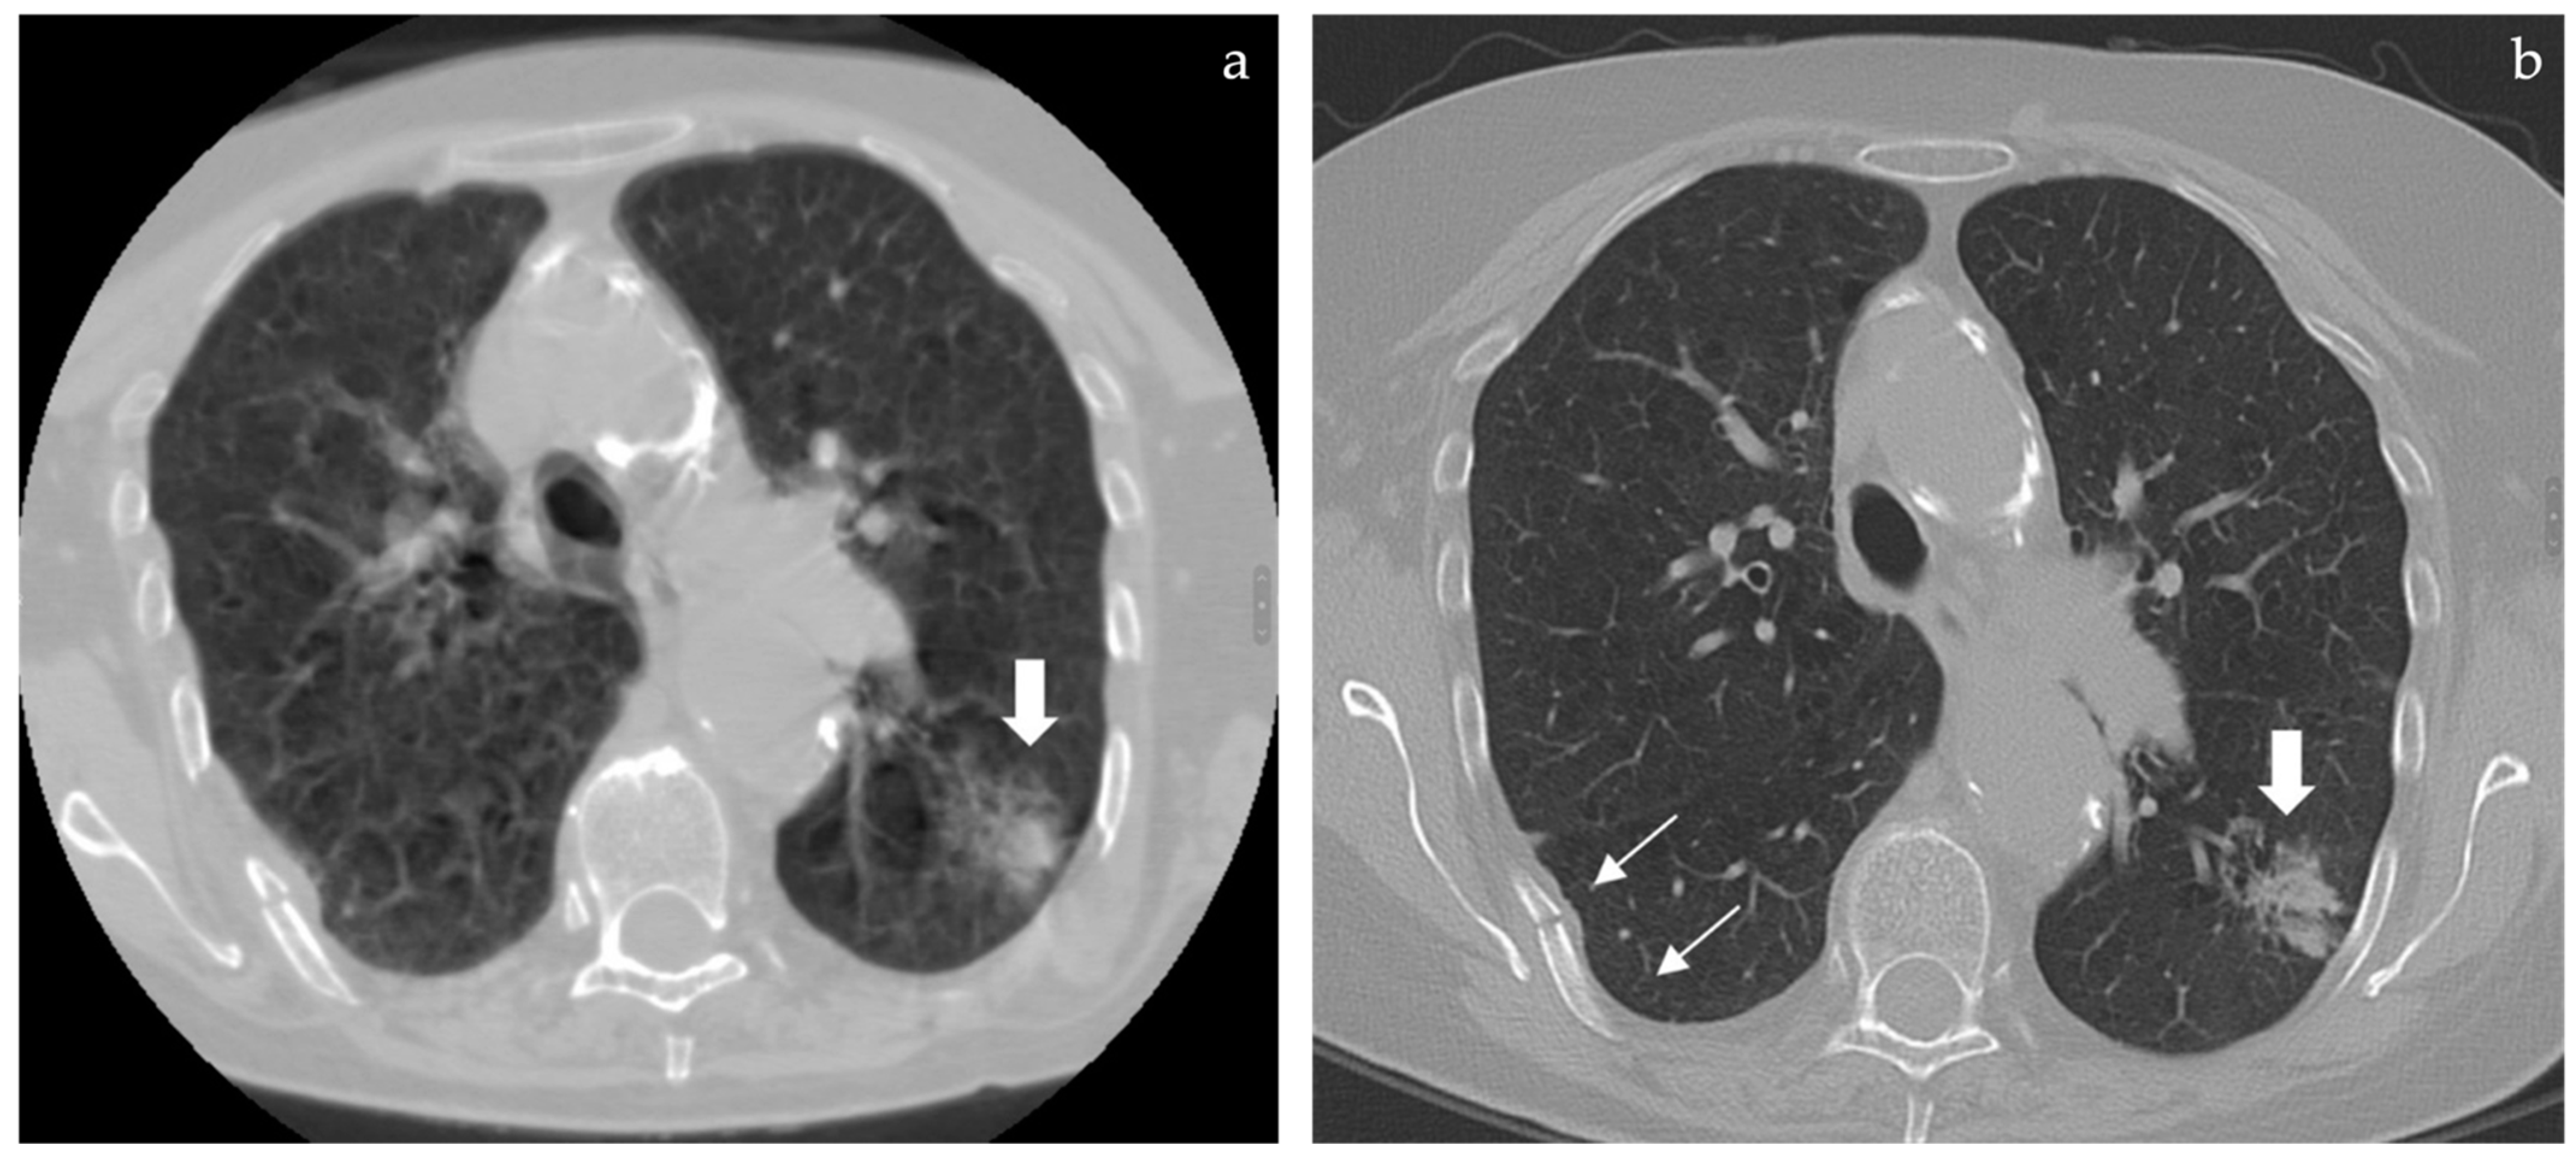

If any pulmonary alteration is even partially included in the field of view, this may appear as a blurry opacity due to breathing artifacts and from a “through the keyhole” perspective due to narrow FOV (Figure 1b,d); whenever these incidental extraspinal findings are noticed, the patient is usually called back to undergo a standard thoracic CT, thus doubling radiation dose, costs, and discomfort of the diagnostic work-up. Given the large portion of thorax left outside the narrow FOV, many more extraspinal findings are hidden to the radiologist even if potentially detectable with the proper technical setting.

Case analysis is shown in Figure 1 and Figure 2.

Figure 2. (a) (left) and (b) (right): whenever a lung opacity is spotted by chance in spine CT a full FOV reconstruction can be performed but only if RAW data are still available in the scanner. In the case (previously described in Figure 1) this allowed us to rule out further opacities but the respiratory motion artifacts prevented a proper characterization of the main lung finding that appeared as a blurry edged opacity (a, large arrow). The patient was called back and a standard thoracic CT was repeated to better define the lung finding that appeared as a subsolid ground glass opacity compatible with a lepidic growth adenocarcinoma (b, large arrow) as later confirmed by lung biopsy. In both full FOV reconstructions a rib fracture was detected (b, thin arrows).